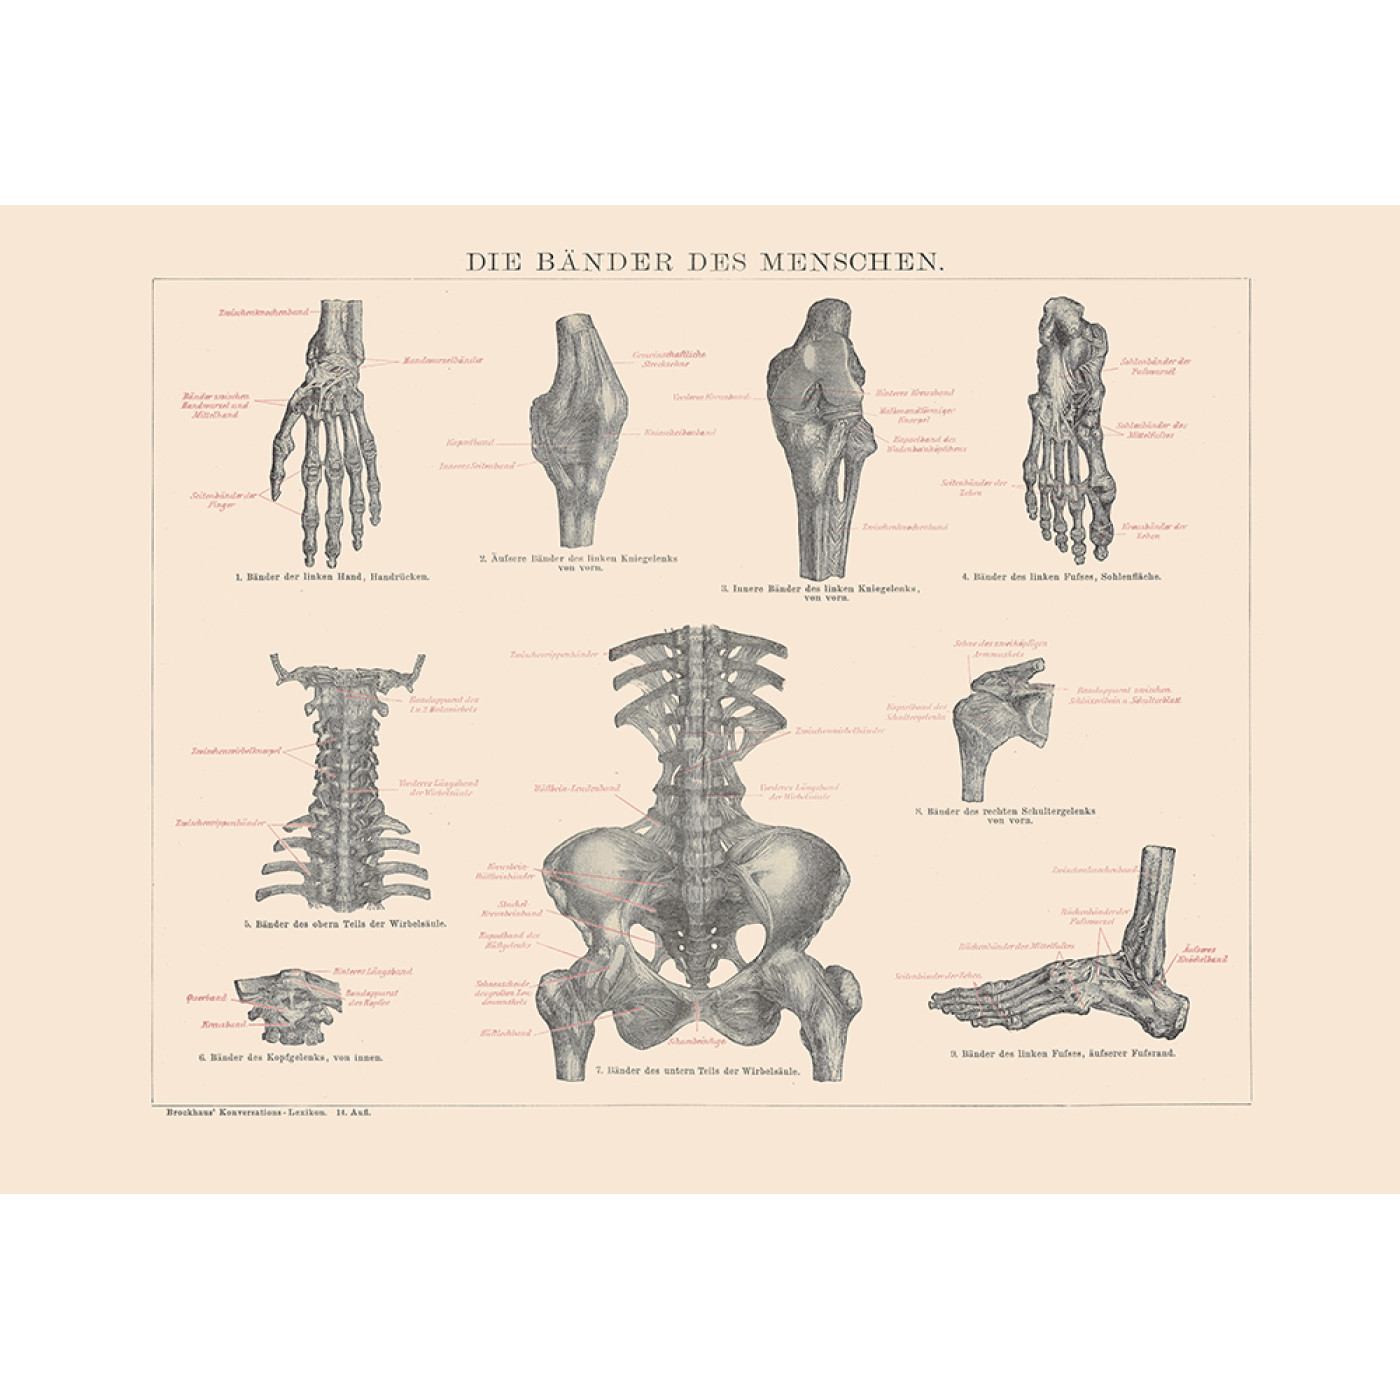

In addition to the information above, here is a curated collection of images related to Ligaments Meaning Types Functions Anatomy Example More.

- Lec 3 - Ligaments Diagram | Quizlet